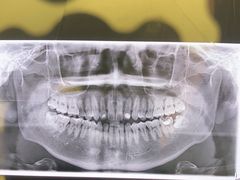

• 安柏口腔(海珠世纪云顶店)

• -安柏口腔(海珠世纪云顶店)